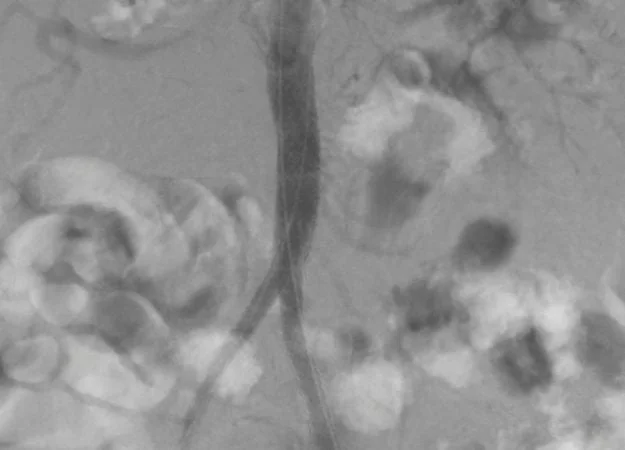

Kết quả chụp CT-Scan ghi nhận, bệnh nhân B. bị tắc hoàn toàn động mạch chủ bụng đoạn dưới động mạch thận, kéo dài đến động mạch chậu ngoài 2 bên.

Bệnh nhân B. được can thiệp nội mạch bằng phương pháp tái tạo ngã ba chủ chậu bằng stent phủ. Sau can thiệp 6 giờ, bệnh nhân B. có thể ngồi dậy, bớt đau chân.

Qua thăm khám, các bác sĩ cho biết, chẩn đoán bệnh nhân T. bị hẹp tắc động mạch chủ bụng và chậu hai bên. Bệnh nhân được can thiệp nội mạch bằng phương pháp tái tạo ngã ba chủ chậu bằng stent phủ; vô cảm và tê tại chỗ.